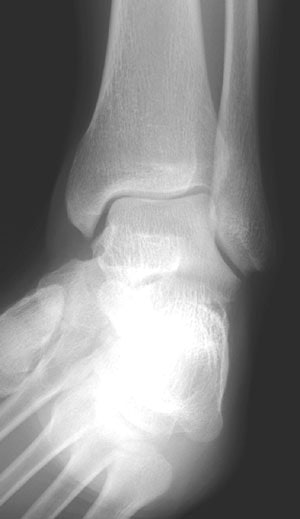

| Mortise view of the ankle; width of the mortise is normal. |